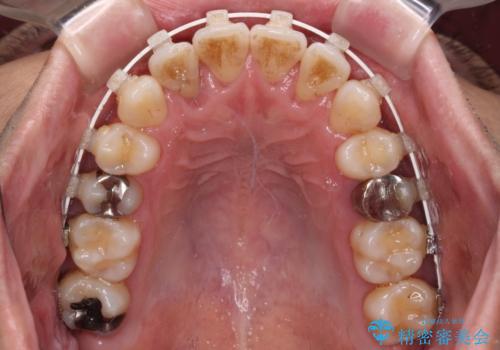

前歯のクロスバイト 目立たないワイヤー装置で矯正治療

- 前歯のクロスバイトを改善したいとのことで来院された患者様です。

マウスピース矯正では前歯の神経への負担が大きいことを懸念され、ワイヤー装置による矯正治療を行うこととしました。

舌の突出癖が認められたため、デコボコ改善に伴い前歯が前突する可能性があったため、舌のトレーニングをしっかりと行うよう指導しながら治療を進めることとしました。